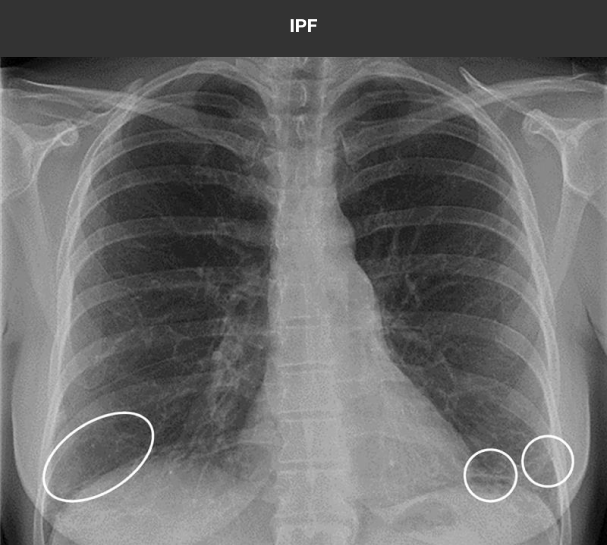

HRCT is the standard in diagnosing ILD9

HRCT allows for the recognition of fibrosis and other abnormalities that may not be apparent on chest x-ray. Below is a comparison of imaging from a 43-year-old female with 3 weeks of sinus congestion and clear sputum production after running:

Case study used with permission from the American Thoracic Society.

Recognizing pulmonary fibrosis early on HRCT is critical18-20

When ILD is suspected in the primary care setting, consider follow-up evaluation by a pulmonologist. Early referral can enable early access to HRCT and multidisciplinary evaluation, the key to early and accurate diagnosis of fibrotic ILDs.